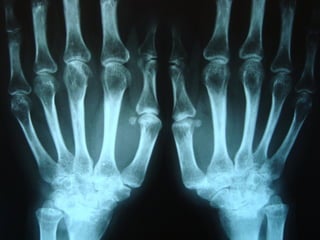

Achados radiográficosAchados radiográficos

 Osteopenia peri-articularOsteopenia peri-articular

 Diminuição do espaço articularDiminuição do espaço articular

 Presença de cisto e erosõesPresença de cisto e erosões

 Edema de partes molesEdema de partes moles

 Presença de deformidadesPresença de deformidades

1- osteopenia 2-erosões 3-sub-luxação